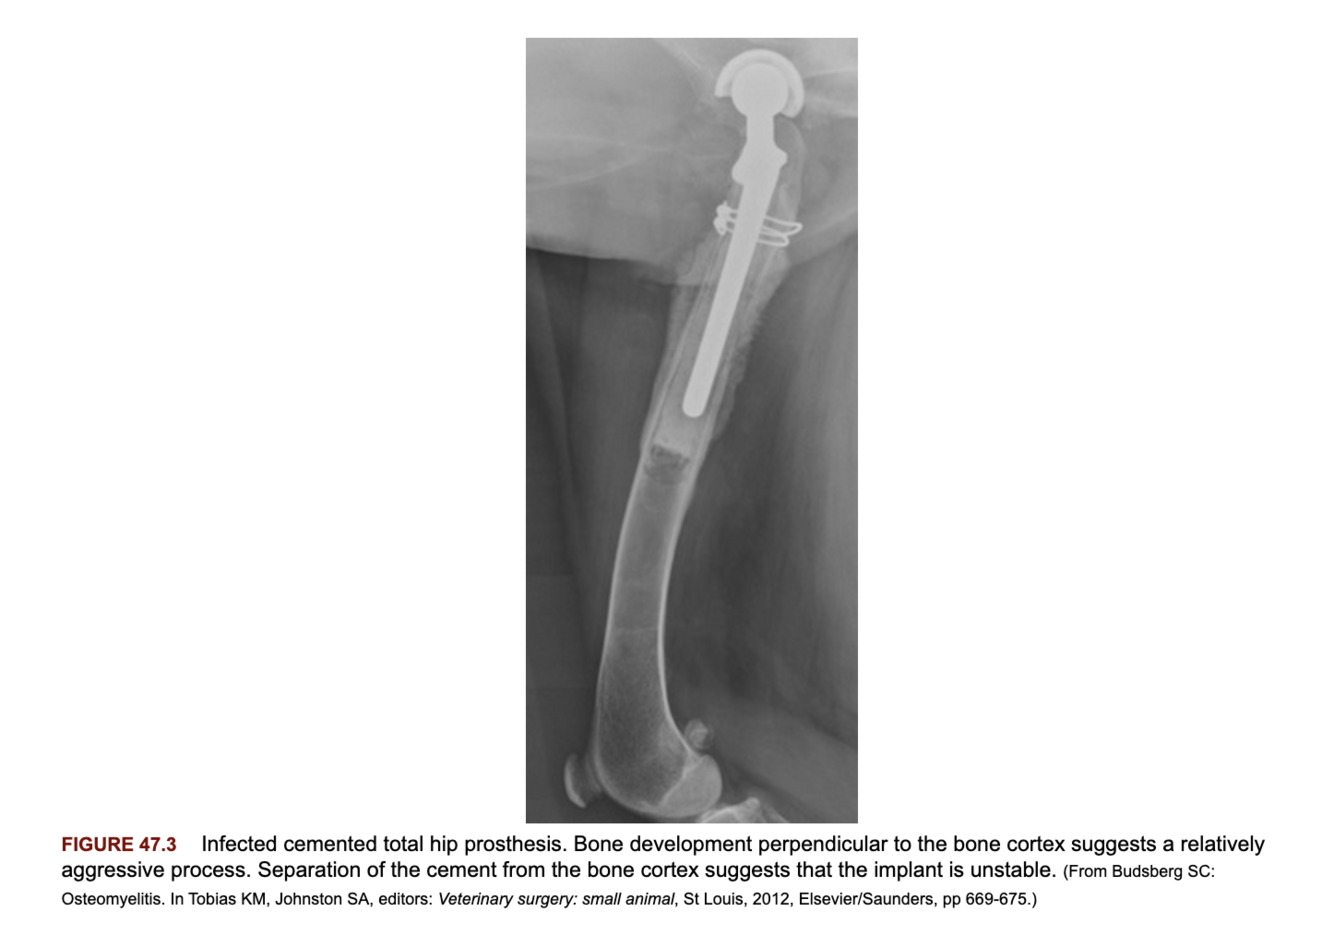

How does the radiographic appearance of aggressive bacterial osteomyelitis differ from less aggressive forms?

A

Less aggressive: slowly separates the periosteum leading to smooth thickening.

Aggressive: new lamellar bone is deposited, this is often perpendicular to the periosteum